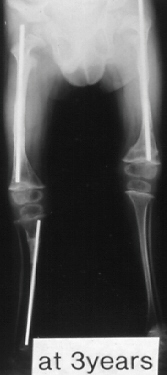

A 20-year-old -male. Body height 145cm. Sillence type I.

The first visit was 3 years of age. He sustained 12 fractures in L/E and underwent 16 operations. He had no scoliosis. Initial gate was obtained when he was 18 months old. He had been a practical ambulator until 16 years old. He can walk 100m on crutches, however, he rather depends upon a wheelchair after he went to high school because of a fear of fractures and convenience for quick transportation. The diameter of the femur has been over 10 mm since 3 years old and is 17 mm now.